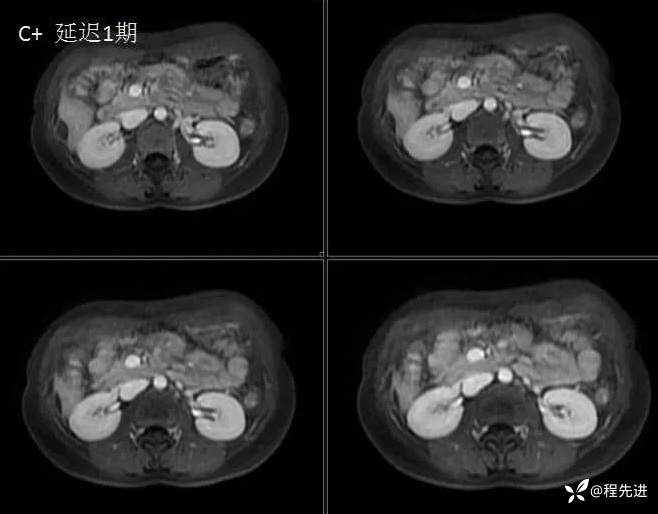

MRI检查: